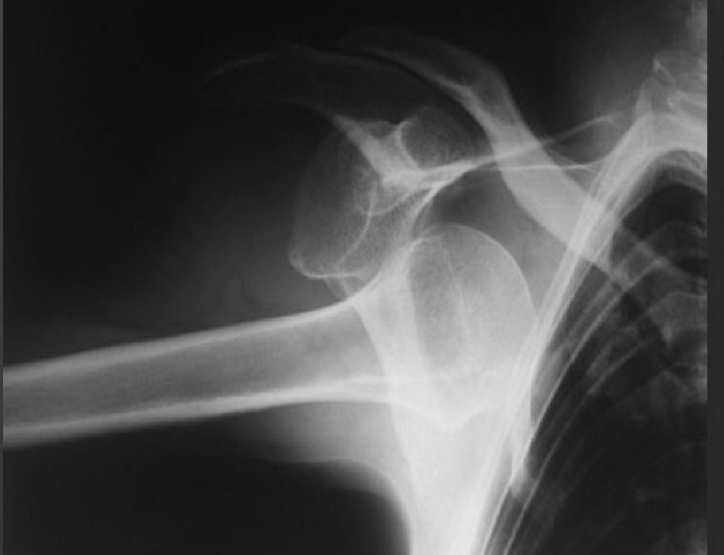

anterior humoral dislocation